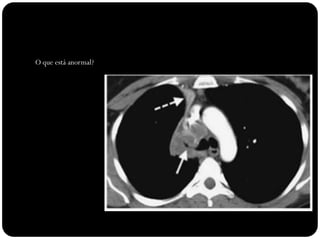

O que está anormal?

Brônquio traqueal

aberrante